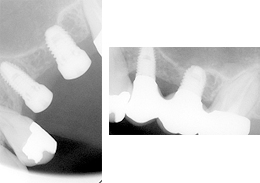

ショートインプラントの症例写真

ショートインプラント使用し骨造成をしないグラフト術式

- 主訴

- 左上ブリッジの支台であった左上5を歯根破折でばっしとなり左上56の欠損となった

- 治療内容

- 抜歯から3ヶ月の治癒期間を経てCT撮影を行った結果、通常であれば上顎洞挙上手術の対象となるケースが多いが、ショートインプラントを用いることで大規模な骨造成お回避できることがわかった。2本ショートインプラント埋入

- 治療費用

- 900,000円(税別)

- 治療期間

- 5ヶ月